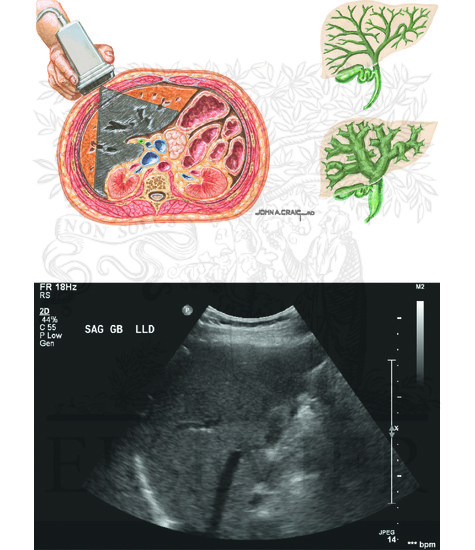

Imaging of the liver and pancreas – Vet Focus

Ultrasound of the liver, biliary tract, and pancreas | Abdominal Key

Imaging Studies of the Liver: Ultrasound